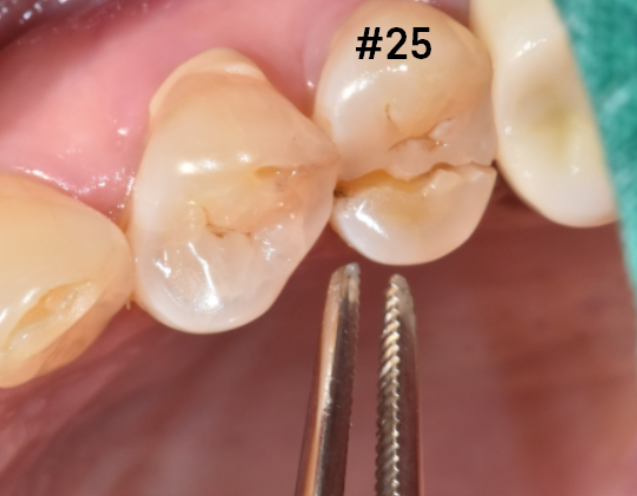

입안 검사를 해보았습니다.

치아가 반으로 쪼개졌네요.

제발 아니길 바랐는데ᅲᅲ

예상한 게 딱 맞았습니다.

이런 경우가

치아가 쪽이 나간 경우입니다.

주로 딱딱한 음식을 잘못 씹었을 때

치아 쪼개짐이 발생하는데요.

이건 치아가 반으로 분리된 거라

발치 후 임플란트 계획을 잡았습니다.

치아 쪼개짐 옆에 잇몸에서도 농이 나오네요

농 = 고름

치아 잇몸 뼈를 계속 녹이는 상황이라

문제가 되는 치아 2개를 발치 후 임플란트 하기로 하였습니다.